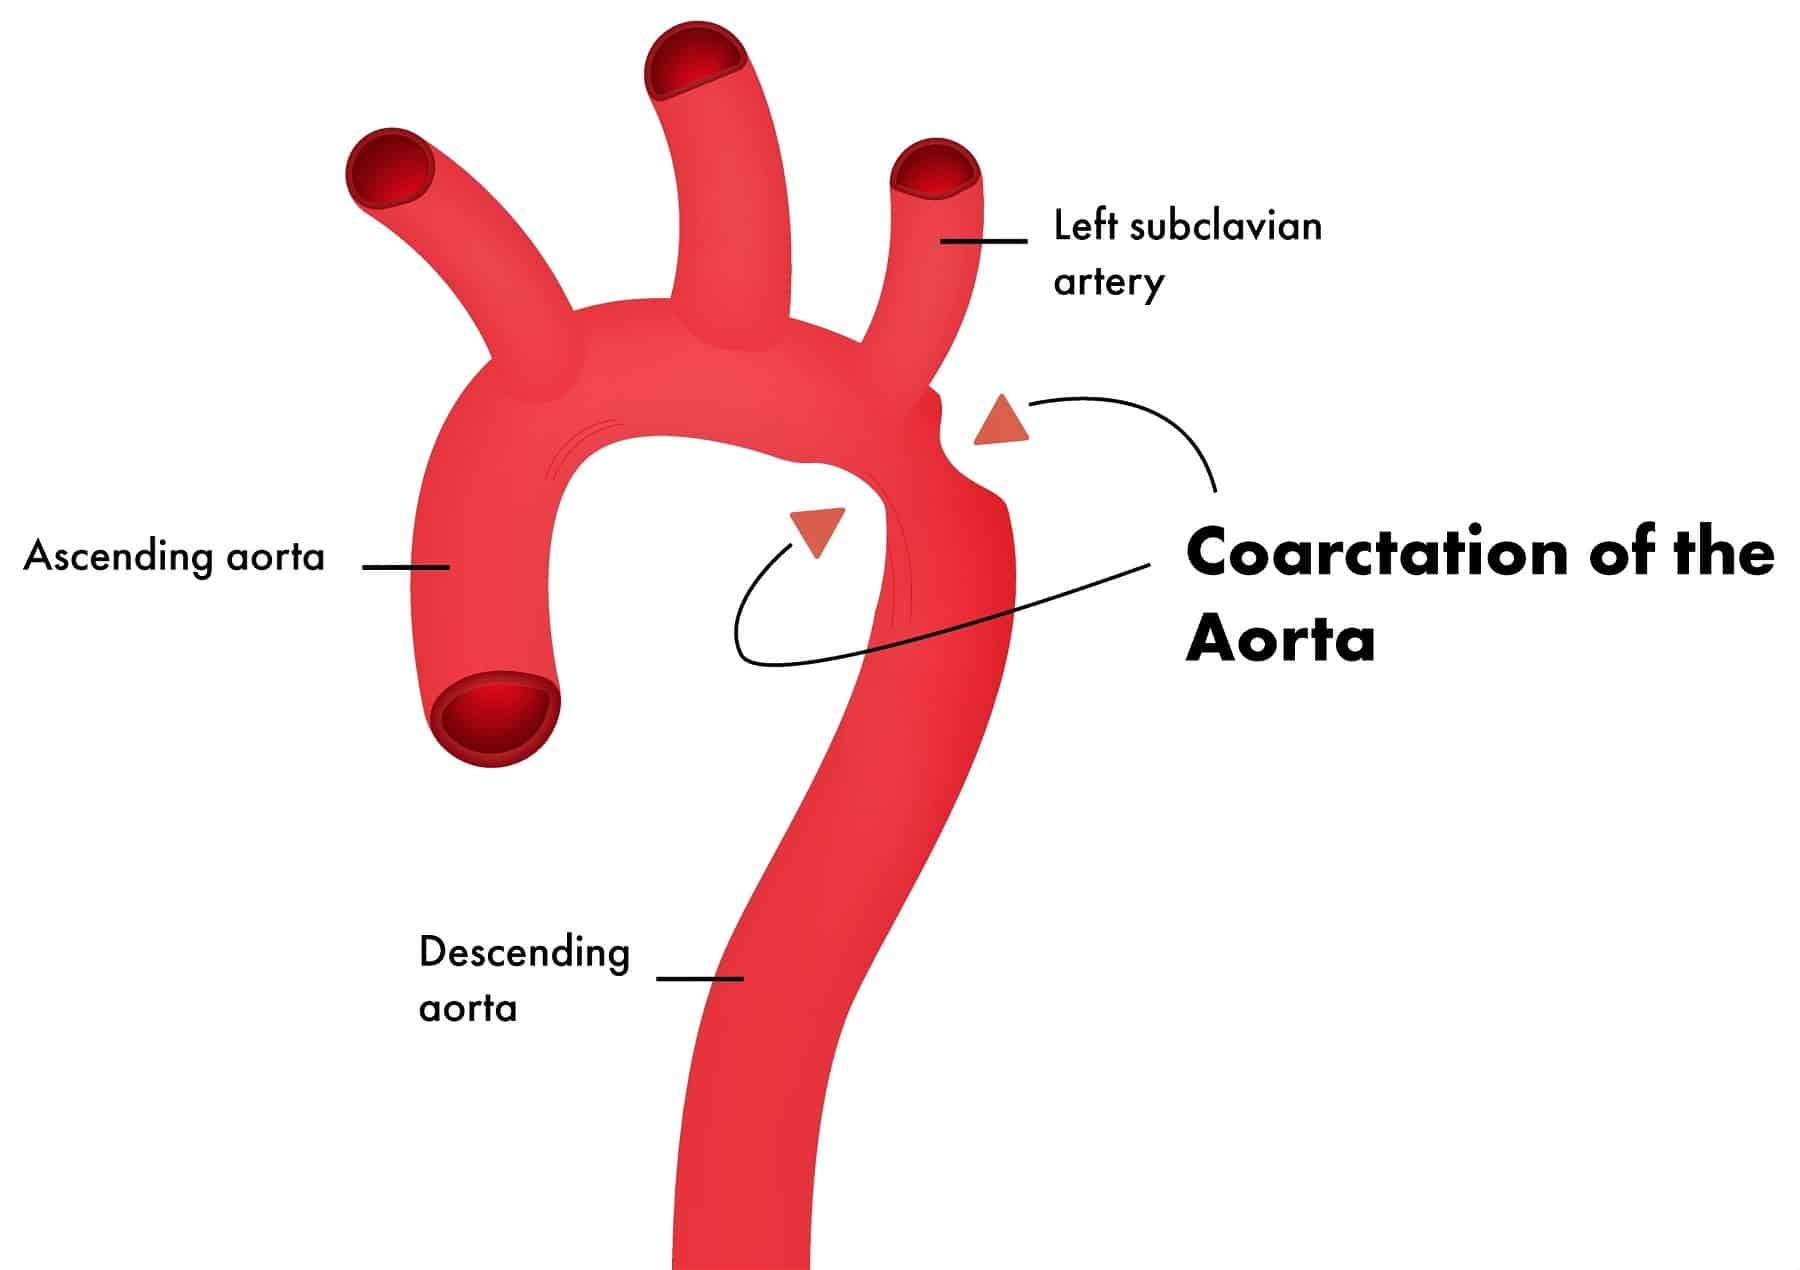

– Quai động mạch chủ thường nằm bên phải (25%)5. Hẹp eo ĐM chủ

– Hẹp eo động mạch chủ trẻ em thường nằm trước vị trí ống động mạch, còn người lớn thường nằm sau ống động mạch

+ Phì đại thất trái

+ Mất ấn động mạch chủ

+ Hình số 3 của động mạch chủ: khuyết lõm số 3 là chỗ hẹp, hai chỗ cong là do cung động mạch chủ và phần ngang động mạch chủ đoạn xuống

+ Khuyết sườn (Dấu hiệu Roesler): khuyết bờ dưới cung sườn do giãn động mạch gian sườn. Thường ảnh hưởng các xương sườn 3 đến 8

+ Tuần hoàn phổi thường bình thường